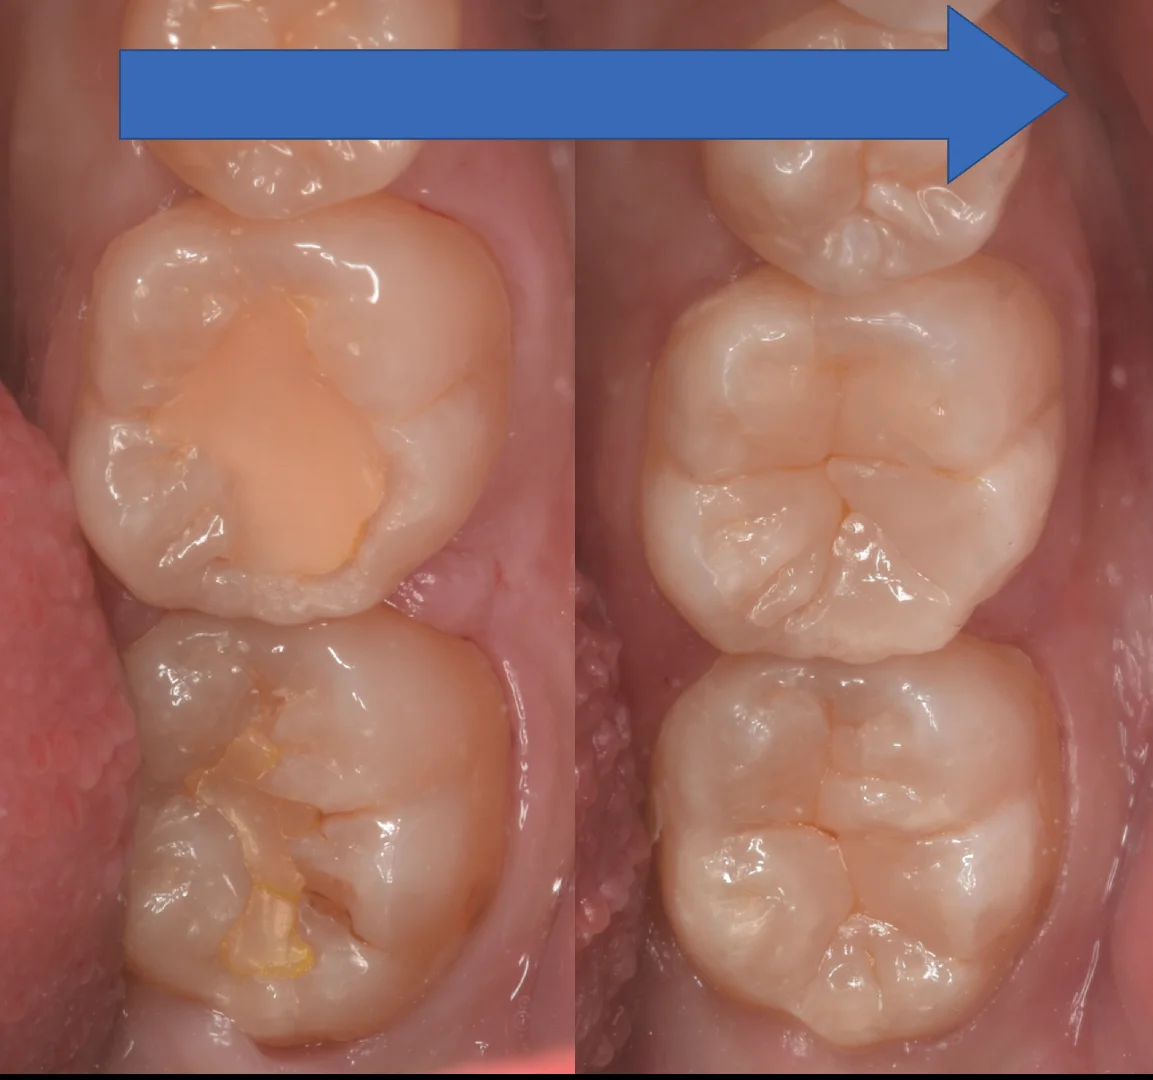

詰め終わって諸々の調整が終わったのがこちらになります。

結構歯の形がしっかりと残っている方だったので、比較的こんもりとした形態にしました。

特に違和感はなく仕上げられたかと思います。

術前術後です。

長時間の治療、お疲れ様でした!